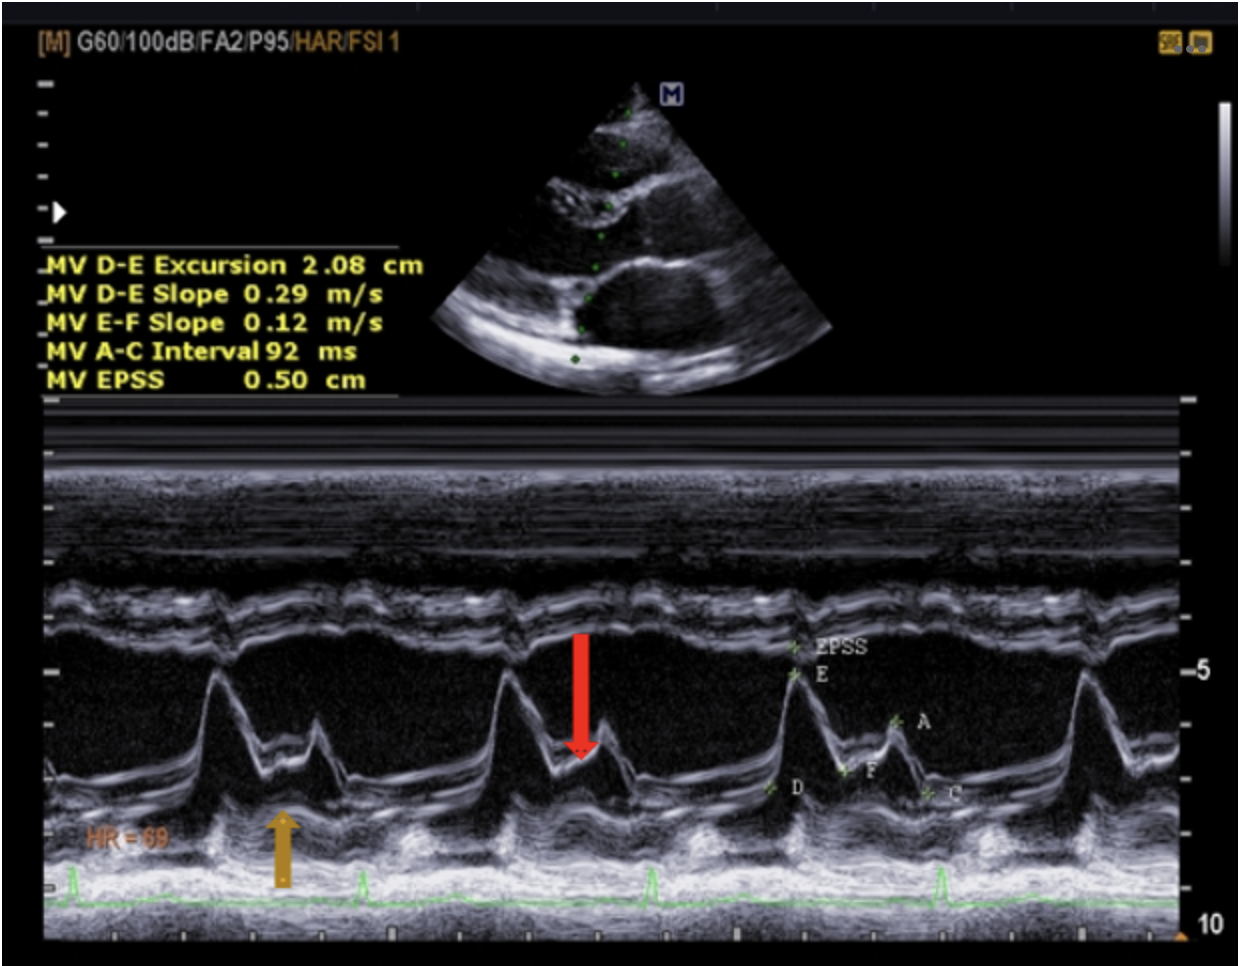

Q

Identify the structure at the gold arrow.

A

d) PMVL